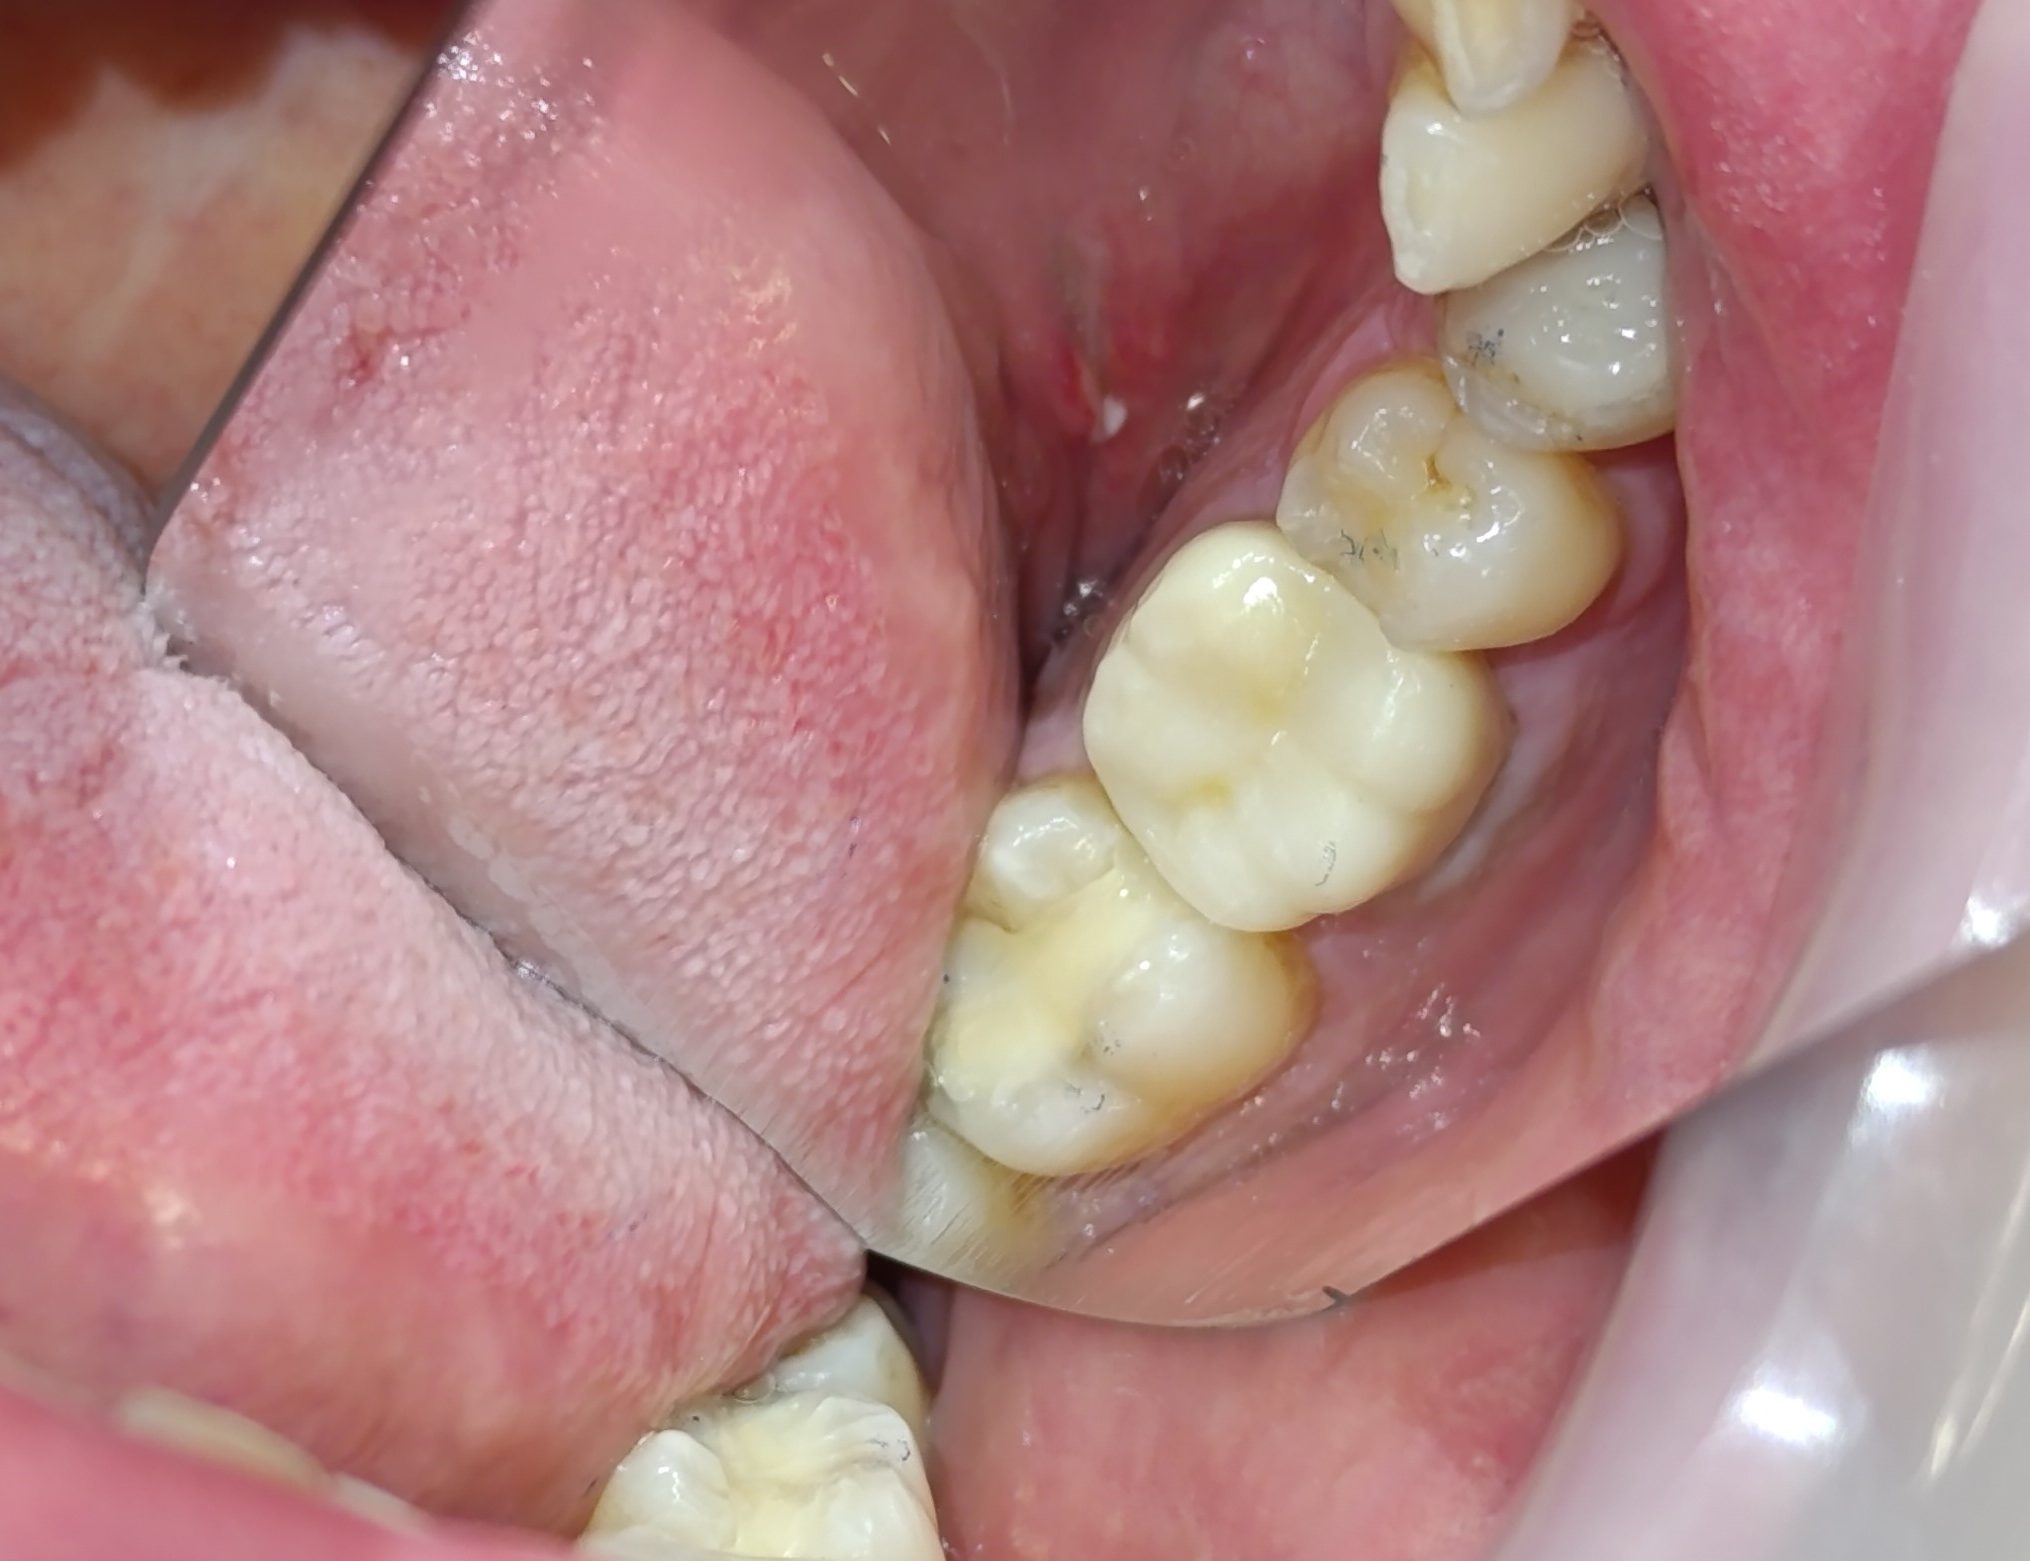

Αρχική κλινική εικόνα του μεγάλου οδοντικού ελλείμματος

Τελική κλινική εικόνα του ολοκεραμικού επένθετου στο γομφίο